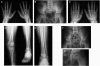

Stickler syndrome is characterized by ophthalmic, articular, orofacial, and auditory manifestations. It has an autosomal dominant inheritance pattern and is caused by mutations in COL2A1, COL11A1, and COL11A2. We describe a family of Moroccan origin that consists of four children with Stickler syndrome, six unaffected children, and two unaffected parents who are distant relatives (fifth degree). All family members were clinically investigated for ear, nose, and throat; ophthalmologic; and radiological abnormalities. Four children showed symptoms characteristic of Stickler syndrome, including moderate-to-severe sensorineural hearing loss, moderate-to-high myopia with vitreoretinopathy, and epiphyseal dysplasia. We considered the COL9A1 gene, located on chromosome 6q13, to be a candidate gene on the basis of the structural association with collagen types II and XI and because of the high expression in the human inner ear indicated by cDNA microarray. Mutation analysis of the coding region of the COL9A1 gene showed a homozygous R295X mutation in the four affected children. The parents and four unaffected children were heterozygous carriers of the R295X mutation. Two unaffected children were homozygous for the wild-type allele. None of the family members except the homozygous R295X carriers had any signs of Stickler syndrome. Therefore, COL9A1 is the fourth identified gene that can cause Stickler syndrome. In contrast to the three previously reported Stickler syndrome-causing genes, this gene causes a form of Stickler syndrome with an autosomal recessive inheritance pattern. This finding will have a major impact on the genetic counseling of patients with Stickler syndrome and on the understanding of the pathophysiology of collagens. Mutation analysis of this gene is recommended in patients with Stickler syndrome with possible autosomal recessive inheritance.